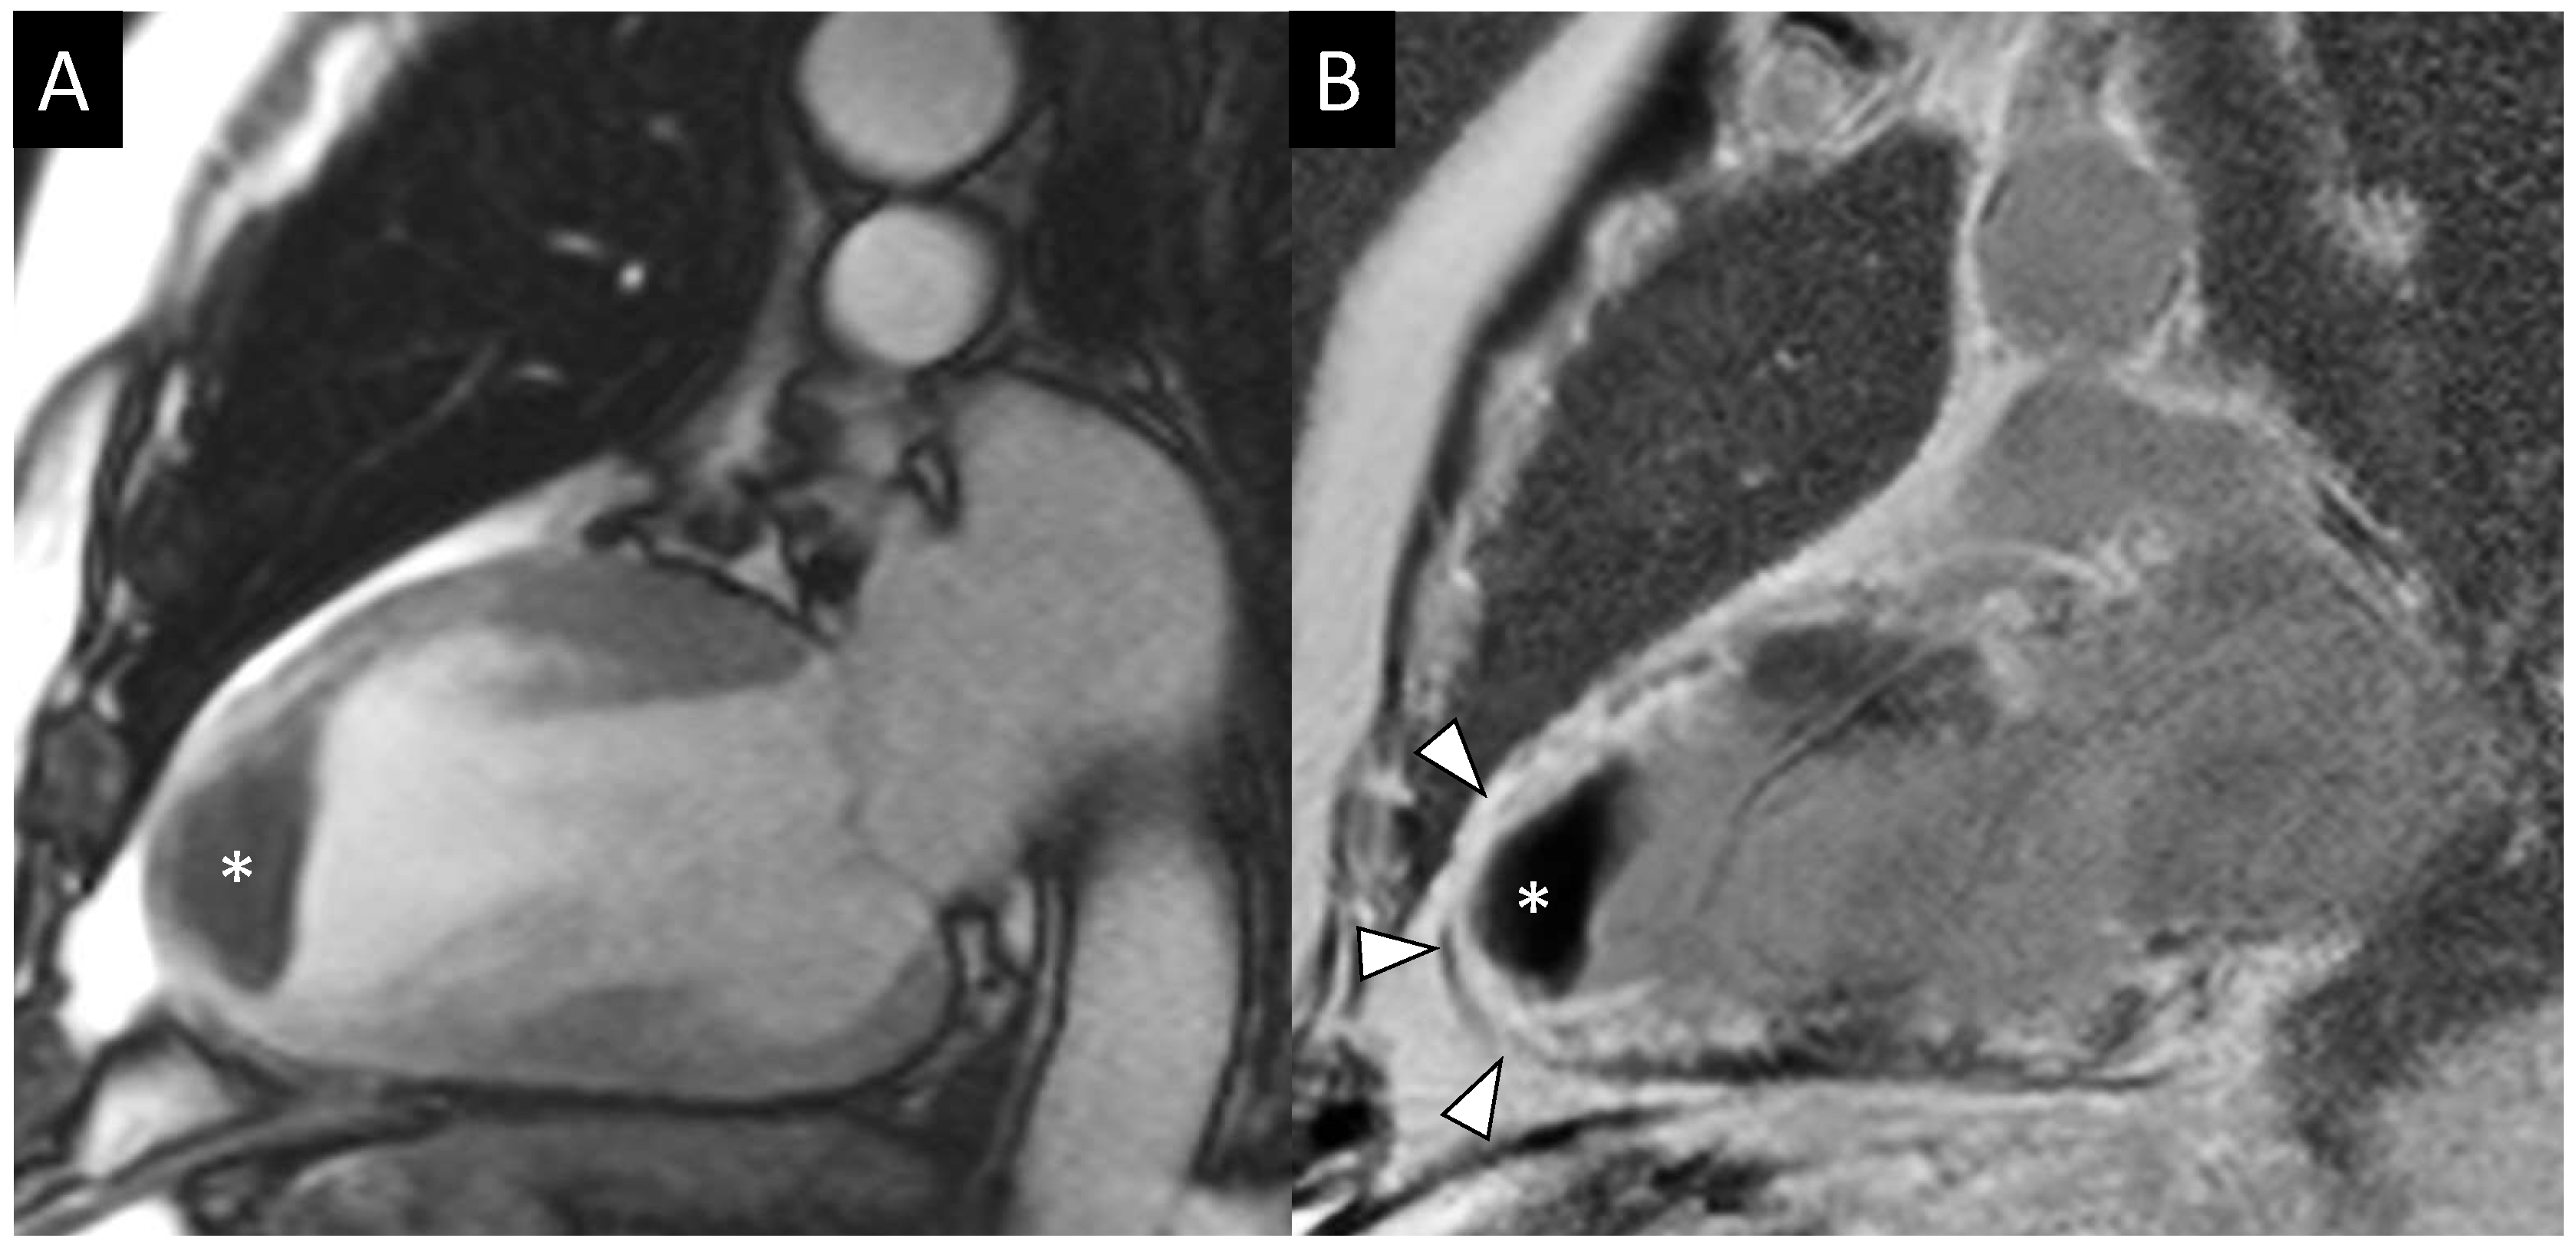

4.1. LGE, MVO, and IMH

- Calvieri, C.; Masselli, G.; Monti, R.; Spreca, M.; Gualdi, G.F.; Fedele, F. Intramyocardial hemorrhage: An enigma for cardiac MRI? Biomed. Res. Int. 2015, 2015, 859073. [Google Scholar] [CrossRef]